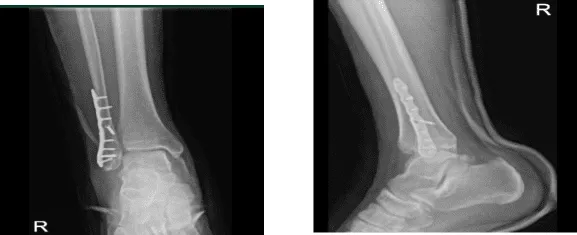

A week after the surgery, the patient visits the office with an X-Ray result, and there is a surgically treated fracture of the distal fibula. Fixation plates and multiple screws are in place. Fracture fragments are in good position and alignment.

Right tibia demonstrates intact cortical margins with no evidence of an acute fracture. Visualized aspects of the right talus, calcaneus and tarsal bones demonstrate intact cortical margins with no evidence of an acute fracture. There are no significant degenerative changes.

Ankle mortise is well maintained and no appreciable soft tissue swelling. There is no calcaneal plantar spur. Status post ORIF distal fibular fracture. Fracture fragments are in good position and alignment. The patient is doing well after the surgery, elevating, and icing.

He still uses aspirin as pain relievers, he denies fever, chills but still he is NWB and using crutches. After two weeks, the patient’s skin peeling over the incision is getting better, the dressing performed with bacitracin, the splint is to continue for 2 weeks more. The patient was advised for 2 weeks for boot application.

X-ray right ankle – 2 weeks after surgery